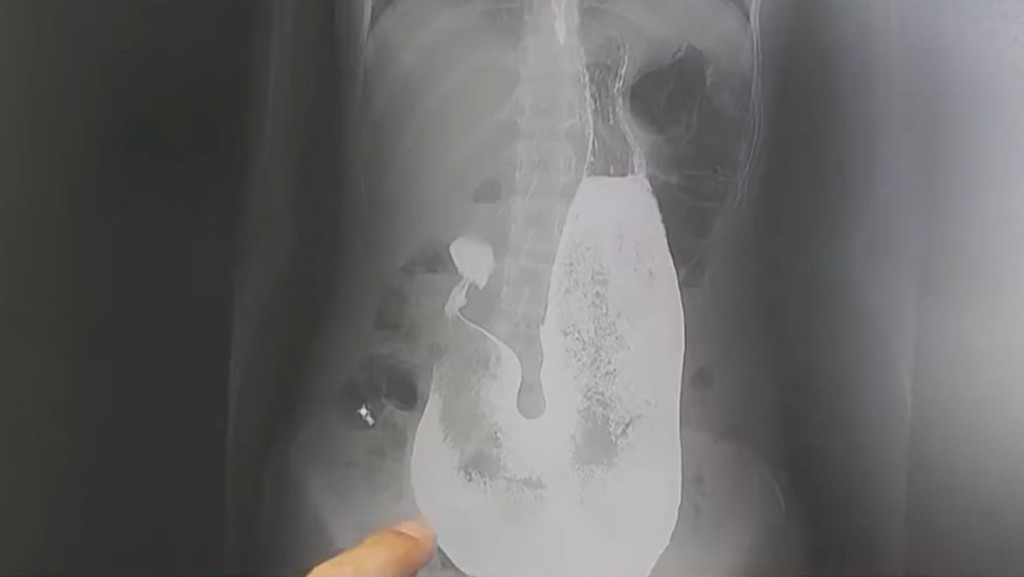

据报道,该名14岁少女是一名“留守儿童”,她的父母长期不在家,在城里工作,女儿则交由农村的爷爷嫲嫲照顾。近日爷爷嫲嫲发现孙女有异样,经常什么也吃不下,头发愈来愈稀疏,怕她身体出问题,于是带她到西安大兴医院检查,医生为少女照胃镜时,发现了胃内一大旧东西,仔细检查后发现,这个是一个达3公斤的“胃发石”,另有一部分头发进入了肠道引起肠梗塞。

医生指“胃发石”是少女将头发吞入胃部后,毛发被胃部的消化液黏在一起所形成的一团毛球。由于少女胃部的“胃发石”实在太大,导致她的胃部被挤得没有空间,因此她才会一直没有食欲,也严重影响她吸收营养。